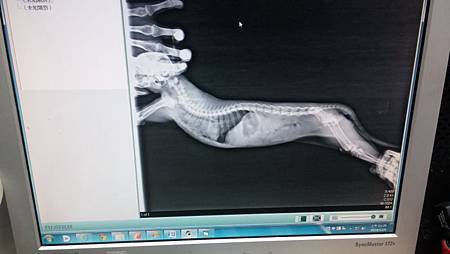

當時於中日動物醫院照X光發現胸腔有氣血胸或肺部破裂,

胸腔有氣血胸或肺部破裂,因X光顯示出肺部及腹部積液,

小貓現仍無法站起,懷疑頸椎處有受傷,

但仍需再評估,懷疑前腳有骨折或脫位(因前肢不正常擺位),